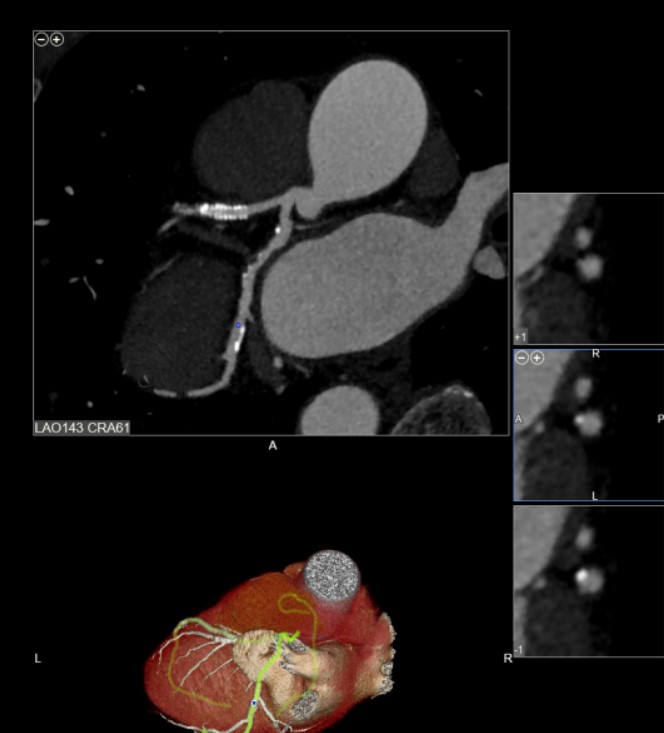

2020 update: My 640 slice CTA , Nov 2019

Hoping to have had some reversal but no luck despite 6.5 yrs following Dr Esselstyn's and others Plant based program to the T, However! still pushing forward with hopefully just a modest increase in the disease year to year. Guess we are all different. A vitamin A,D and K2 protocol was observed for the last 3 years. |

CTA's were taken on 2-2017 and 11- 2019 app. 34 months apart on the same Toshiba Aquillion

Total calculated Agatston score (excluding stent) is: 414 ( prior 382) LAD: 209 (prior 210) LCX: 197 (prior 171) RCA: 8 (prior 1)

2020 photo courtesy of Dr Shaw, showing stent in LAD and disease in LCX

end view of an artery seen on right side. Below 2020

2020 curved multi planar images showing stent in LAD(left) and disease in LCX tks Dr. Shaw for great images, end view of arteries are seen on right. |